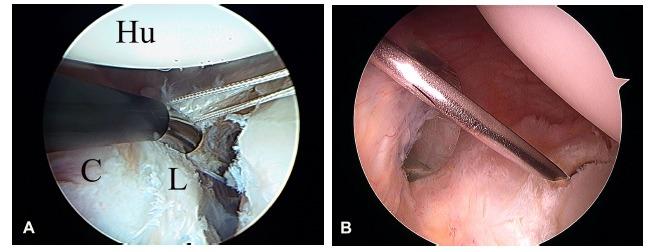

Arthroscopic double-pulley remplissage technique for engaging Hill-Sachs lesions in anterior shoulder instability repairs.关节镜下双滑索填充技术治疗前肩不稳修复术中的 Hill-Sachs 损伤。

Arthroscopic osseous Bankart repair for chronic recurrent traumatic anterior glenohumeral instability.关节镜下骨性Bankart修复术治疗慢性复发性创伤性前盂肱关节不稳

Arthroscopic labral repair and capsular shift of the glenohumeral joint: technical pearls for a multiple pleated plication through a single working portal.肩关节镜下盂唇修复及盂肱关节囊移位:经单一工作通道进行多重折叠襞成形术的技术要点